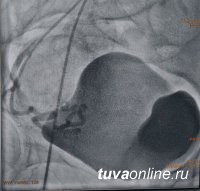

Пациентка Н.. 43 лет, была направлена в РСЦ на проведение эмболизации маточных артерий по поводу миомы матки гинекологами Перинатального центра РТ. Пациентка жаловалась на периодические ноющие боли внизу живота, длительные и обильные менструации. Под местной анестезией ей была выполнена пункция бедренной артерии специальным катетером, далее по нему проведен проводниковый катетер, через В Туве впервые выполнена высокотехнологичная операция по миоме маткикоторый выполнялась селективная эмболизация маточных артерий миоматозных узлов специальными микросферами. Это позволяет прекратить приток крови к опухолевым миоматозным узлам.

В результате опухоль перестает расти и постепенно значительно уменьшается или вовсе исчезает.